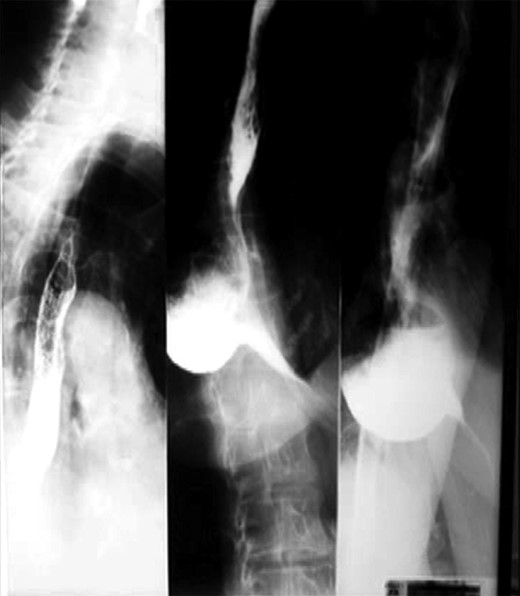

A 78-year-old Caucasian woman presented with recurrent dysphagia, slight tenderness in the epigastrium and substantial weight loss. Difficulty with solid food digestion and regurgitation were present for almost 10 years. The symptoms had exacerbated four months before intervention during which period the patient was fed through a nasogastric tube. CT scan, barium swallow (Fig. 1) and esophagogastroduodenoscopy showed a large mid-esophageal diverticulum. The neck of diverticulum was within 5 cm of the carina and was 4 cm wide. The diameter of the sac reached 10 cm, and narrow esophagogastric junction suggested achalasia, which was confirmed by manometry. The patient suffered a heart attack 3 years ago and has secondary dilatative ischemic cardiomyopathy. Due to cardiac co-morbidities, surgical intervention was graded as a high-risk procedure (ASA III), with patient’s quality of life being crucial in decision making. The patient was placed in supine position in reverse Trendelenburg with five ports placed as earlier described for transhiatal epiphrenic diverticula operations [7]. Throughout the procedure the esophagoscopic image was provided by an interventional gastroenterologist and dissection was performed under the guidance of both laparoscopic and endoscopic image (Fig. 2). This was essential due to a very narrow operating field and a lack of orientation points. The liver was retracted, and crura of the diaphragm were dissected with Ultracision (Ethicon Endo-Surgery Inc., Cincinnati, OH, USA) (Fig. 3), after which mediastinum was entered. The esophagus was bluntly dissected around its entire circumference and the gastroesophageal junction was encircled with an umbilical tape to ensure easier traction. The diverticulum was approached by both blunt dissection and electrocauterization. Resection of the wide neck of diverticulum was done with EndoGIA (Covidien, Mansfield, MA, USA) (Fig. 4). Another cartridge was used for dissection of the superior portion of the diverticulum. Possible air leakage was tested by irrigation of the field and was negative. Dissected diverticulum was withdrawn from the mediastinum and placed into an endobag. Heller myotomy was performed 5 cm orally and 2 cm distally from the gastroesophageal junction for reduction of achalasia. After the cruroplasty had been performed, the anterior fundus wall was sutured to the muscular edges of myotomy (Dor fundoplication) to prevent possible postoperative complications, such as gastroesophageal reflux disease (GERD). Operating time was 6 h, and the procedure went without any complications.

Preoperative barium swallow. The preoperative barium swallow images showing a 10 × 8 cm diverticulum whose 4 cm wide neck was situated ~5 cm from the carina.